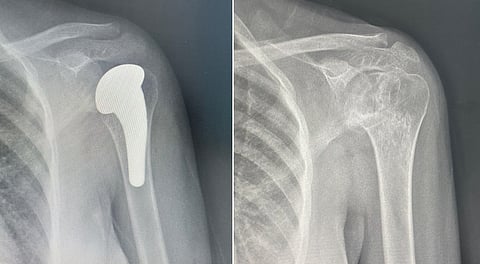

وأوضح الدكتور فهد بن حمد الحليبي، استشاري جراحة العظام والإصابات الرياضية والمناظير، أن المريضة كانت تعاني من تآكل متقدم في رأس عظمة العضد وآلام مزمنة في مفصل الكتف، أثّرت بشكل كبير على جودة حياتها وقدرتها على الحركة.

وأشار إلى أن المريضة خضعت لمحاولات علاجية تحفظية عدة لم تحقق نتائج مُرضية، ما استدعى التدخل الجراحي بعد تقييم شامل وفحوصات دقيقة.

وأكد الدكتور الحليبي أن المريضة دخلت فعليًا مرحلة التعافي، مع تحسن تدريجي في الحركة وتراجع ملموس في مستوى الألم.